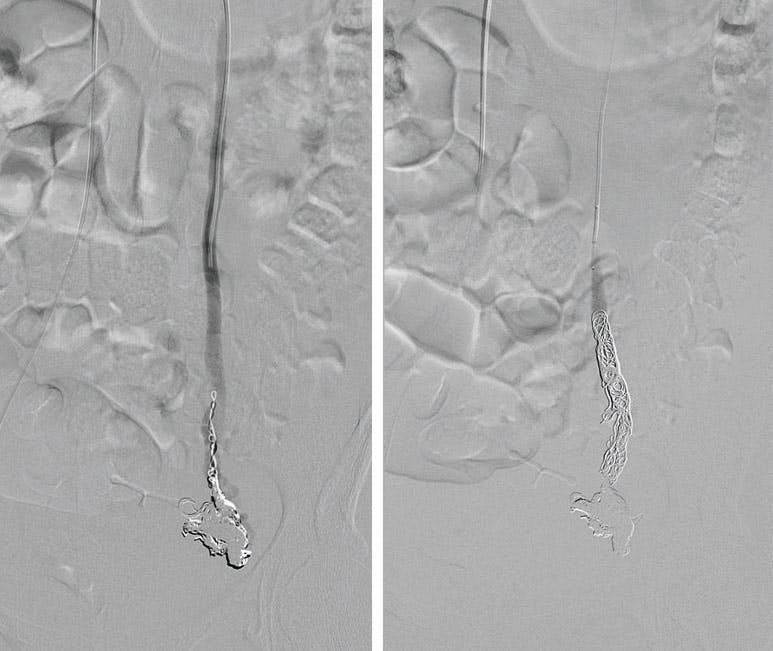

PROCEDURE

Selective venography confirmed reflux in the left gonadal vein with filling of parametrial tributaries (Figure 2 and Figure 3). Embolization was performed using 0.018-inch Ruby Coils, requiring only four coils for the entire case (Figure 4). A single 14-mm X 60-cm Ruby Coil was deployed in the main left gonadal vein, followed by three 10-mm X 35-cm Ruby Coils in the left parametrial veins. The broad range of available diameters and lengths allowed for accurate sizing without excessive coil oversizing, facilitating efficient occlusion while potentially reducing vein wall irritation and postprocedural pain. To further reduce the risk of future collateral recanalization, the proximal left gonadal vein was capped with 1 mL of n-Butyl cyanoacrylate (NBCA) mixed with ethiodized oil in a 3:1 ratio (Figure 5).

Figure 2. Venography showing reflux within an enlarged left ovarian vein.

Figure 3. Venography showing cross venous reflux within the parametrial veins.

Figure 4. Successful embolization with complete stasis after 0.018 Ruby Coil deployment.

Figure 5. Final spot image after the addition of NBCA emulsion.